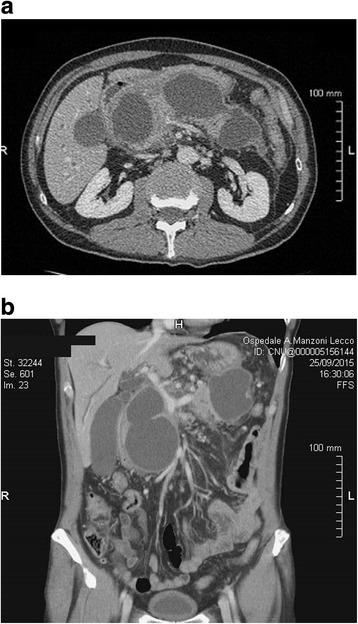

We describe a case of a 64-year old man with large multiple pancreatic cysts discovered for progressive jaundice and significant weight loss in the absence of a previous episode of acute pancreatitis. Computed tomography scan showed lesion with thick enhancing walls. The main cyst dislocated the stomach and the duodenum inducing intra and extrahepatic bile ducts enlargement. Magnetic resonance cholangiopancreatography revealed a communication between the main pancreatic duct and the cystic lesions due to Wirsung duct rupture. Endoscopic ultrasound guided fine needle aspiration cytology did not show neoplastic cells and cyst fluid analysis revealed high amylase concentration. Preoperative exams were suggestive but not conclusive for a benign lesion. Laparotomy was necessary to confirm the presence of large communicating pseudocysts whose drainage was performed by cystogastrostomy. Histology confirmed the inflammatory nature of the cyst wall. Subsequently, the patient had progressive jaundice resolution.

我们描述了一例64岁男性,因进行性黄疸和显著体重减轻发现多个巨大胰腺囊肿,既往无急性胰腺炎发作史。计算机断层扫描显示病变壁增厚且强化。主囊肿使胃和十二指肠移位,导致肝内和肝外胆管扩张。磁共振胰胆管造影显示由于主胰管破裂,主胰管与囊性病变之间存在连通。内镜超声引导下细针穿刺细胞学检查未发现肿瘤细胞,囊液分析显示淀粉酶浓度高。术前检查提示为良性病变,但不能确诊。需要进行剖腹手术以确认存在巨大的连通性假性囊肿,并通过囊肿胃吻合术进行引流。组织学证实囊肿壁具有炎症性质。随后,患者的黄疸逐渐消退。